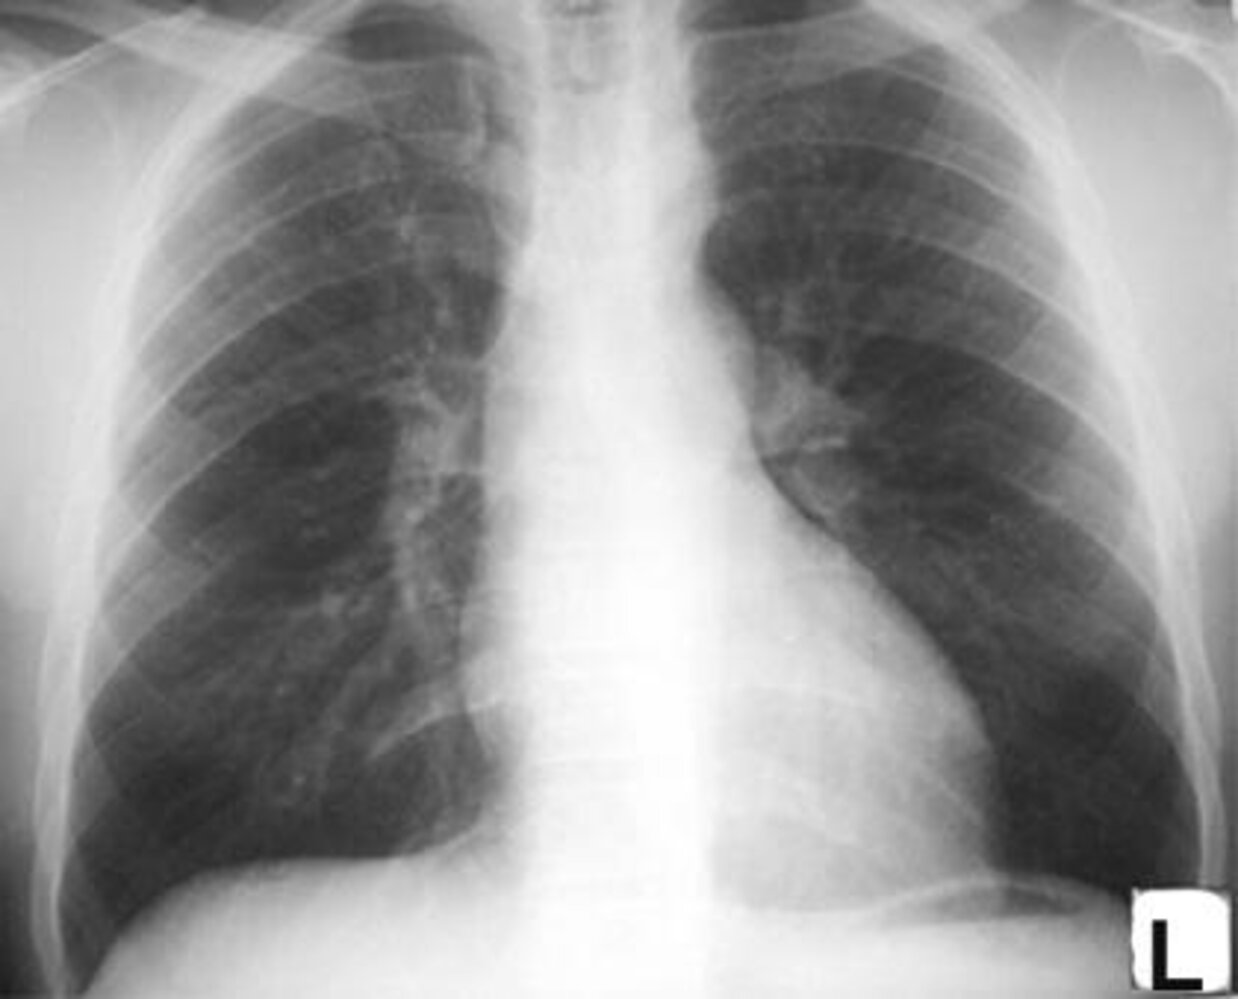

Chest x-ray

- Small defects: normal chest x-ray

-

Medium or large defects

- Enhanced pulmonary vascular markings

- Rounding of the apex and left cardiac contour due to left atrial and ventricular hypertrophy

- Rounding of the mid-left heart border due to right ventricular hypertrophy and enlarged pulmonary artery (in later stages; due to ↑ pulmonary vascular resistance)